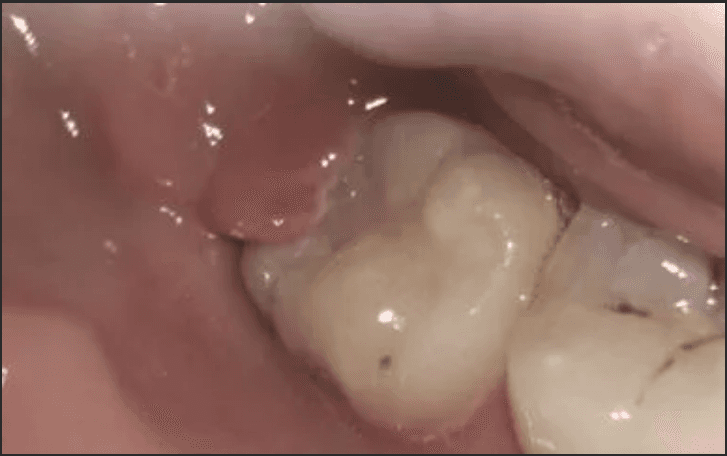

A 25-year-old woman accidentally bit into the thin collar of gum sitting over her lower right wisdom tooth and wanted to consider extraction. Despite being a wisdom tooth, it was a functional tooth with an opposing wisdom tooth to bite against. It was an issue with overlying gum, rather the wisdom tooth itself. After removing the collar of gum, it recovered well without recurrence and she has managed to keep the wisdom tooth to present day without any further issues.

Before